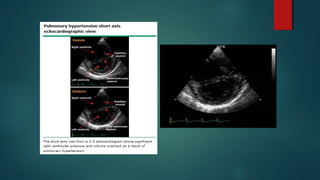

ECOCARDIOGRAMA

 Debe solicitarse siempre ante sospecha de HP.

 Utilidad:

 Estimación de la Presión de la Arteria Pulmonar.

 Tamaño del VD.

 Tamaño de la AD.

 Función Sistólica y Diastólica.

 Función Valvular (principalmente insuficiencia tricuspidea)

 Shunt Intracardiacos.

ECOCARDIOGRAMA  Debe solicitarsesiempre ante sospecha de HP.  Utilidad:  Estimación de la Presión de la Arteria Pulmonar.  Tamaño del VD.  Tamaño de la AD.  Función Sistólica y Diastólica.  Función Valvular (principalmente insuficiencia tricuspidea)  Shunt Intracardiacos. Lewis J Rubin, MD et al. «Clinical features and diagnosis of pulmonary hypertension in adults”. UPTODATE. Literature review current through: May 2015.